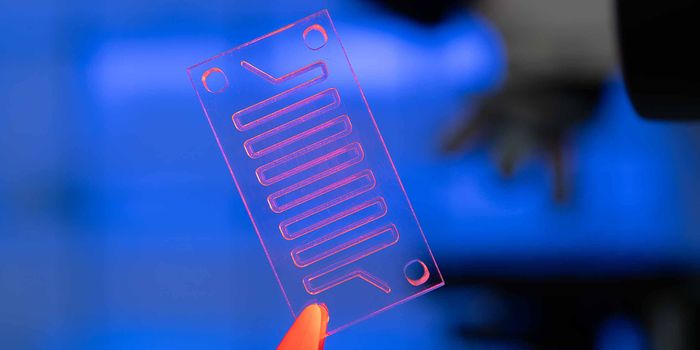

NOV 02, 2016Chemistry & PhysicsDiagnosing Sepsis Earlier to Save Lives Using Microfluidics